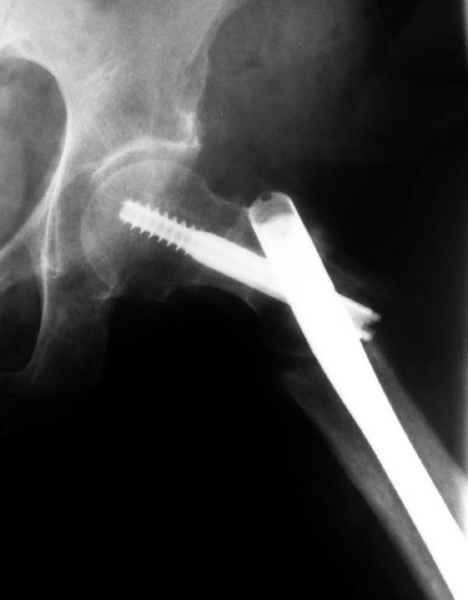

77 летняя больная направлена в нашу клинику на дальнейшее лечение. Из истории, травму получила в сентябре 2007 года и по поводу перелома шейки бедра больная была проперирована тремя каннюлированными шурупами с явным нарушением технологии установки шурупов. Внизу вместо одного шурупа имеется два, что привело к стрессу латерального кортекса. Через месяц по поводу ятрогенного подвертельного перелома сделана фиксация длинной Гамма 3. Установлен без проксимальной блокировки? (set screw). В данный момент имеется несостоятельность конструкции и ложный сустав. Передвигается с помошью костылей, конечность укорочена на 2 см. Какие будут рекомендации?Djoldas Kuldjanov, MDDepartment of Orthopedic SurgerySt. Louis University Medical Center

Я не вижу на снимках нестабильности конструкции (разве что гнутый дистальный винт).

Михаил, здравствуйте. Если присмотреться - на четвертом снимке есть перелом гвоздя по отверстию.

Видимо, проблем тут две: во-1-х, центральный отломок был оставлен в варусно-сгибательной установке, во-2-х, не динамизировали вовремя.

Нижние винты хотели сломаться, но, увы, один не сломался, и тогда сломался гвоздь. Хотя и при динамизации в таком положении отломков

могло не срастись.